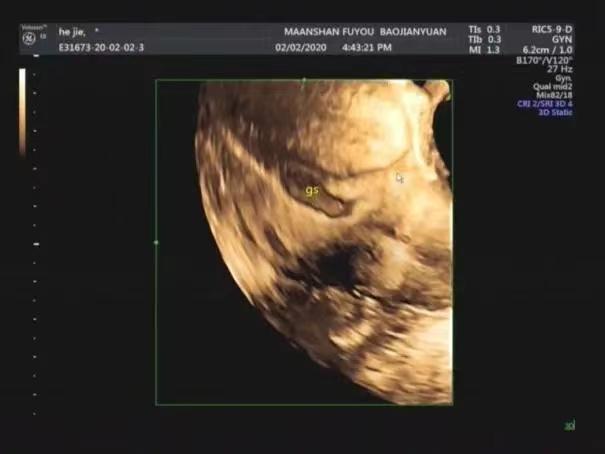

3.子宫瘢痕妊娠的定位。三维超声可直观显示孕囊与疤痕位置关系,对评估妊娠预后及临床治疗提供了重要信息。